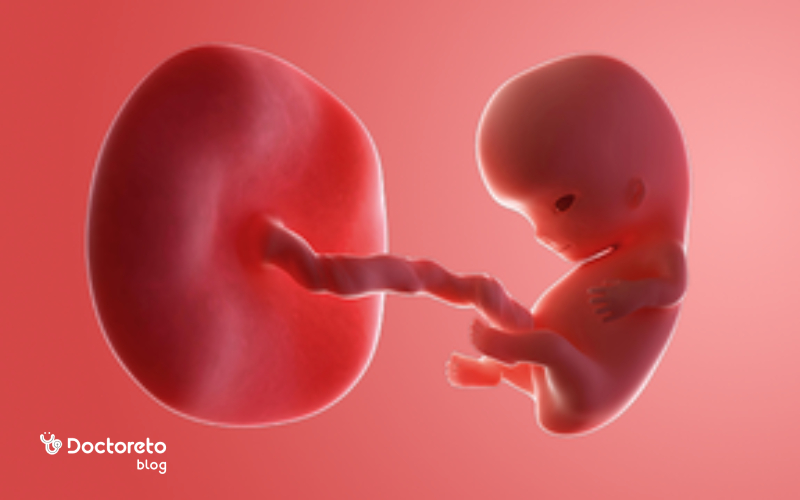

وضعیت جنین در هفته هشتم بارداری

جنین در هفته هشتم بارداری حدود ۱٫۵ تا ۲ سانتیمتر است. سیستمها و اندامهای بدن به رشد خود ادامه میدهند. ویژگیهای فیزیکی جنین بیشتر مشخص میشود. اجزای صورت بهمرور به نوزاد شباهت پیدا میکنند. تغییرات جنین شامل موارد زیر میشود.

- بدن جنین بهمرور صاف میشود و شباهت جنین به قورباغه کمتر میشود. در این هفته دم جنینی از بین رفته و پاها شکل میگیرند.

- جوانههای پاها و بازوها رشد میکنند. انگشتان دست و پا شکل میگیرند.

- سیستم گوارشی جنین بهخصوص روده رشد میکند. البته داخل بدن جنین فضای کافی برای رشد روده وجود ندارد. به همین دلیل به سمت بندناف حرکت میکند. زمانیکه فضای کافی داخل بدن جنین ایجاد شود، روده به سمت محل اصلی خود حرکت میکند.

- بینی و لب بالایی جنین شکل میگیرد.

- چینهای ریز روی پلک تشکیل میشوند.

- در قسمت بیرونی سر جنین گوشها شکل میگیرند. گوشها از داخل هم به رشد خود ادامه میدهند.

- اندام تناسلی جنین در هفته هشتم حاملگی شکل میگیرد و تبدیل به تخمدان یا بیضه میشود. البته هنوز در سونوگرافی نمیتوان جنسیت را تشخیص داد.

در هفته هشتم بارداری، جنین حدود ۱.۵ تا ۲ سانتیمتر طول دارد (تقریباً به اندازه یک تمشک) و وزن او حدود ۱ تا ۲ گرم است. در این مرحله، جنین از حالت تودهای سلولی به شکل یک نوزاد کوچک با سر بزرگتر از بدن تغییر کرده است. اندامهای اصلی مانند قلب، مغز، کلیهها و ریهها در حال شکلگیریاند و بازوها و پاها بهصورت برجستگیهای کوچکی قابل مشاهدهاند. همچنین در سونوگرافی، حرکات خفیف جنین و ضربان منظم قلب معمولاً قابل مشاهده است که نشانه رشد طبیعی اوست.

شکل جنین در هفته هشتم چگونه است؟

در هفته هشتم بارداری، اندازه و شکل جنین شبیه یک لوبیا است و در سونوگرافی نیز به همین شکل دیده میشود. در این مرحله، رشد جنین بسیار سریع است و تقریباً هر هفته اندازهاش دو برابر میشود. اندامهای اصلی مانند قلب، مغز، کبد و کلیهها در حال شکلگیریاند و دستها و پاها نیز بهتدریج از بدن جدا میشوند. این دوره از بارداری یکی از حساسترین مراحل رشد جنین محسوب میشود، زیرا پایههای تمام اندامها در حال تکاملاند.